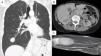

La paciente permaneció asintomática y libre de enfermedad hasta 16 meses del postoperatorio, cuando se detectan múltiples nódulos compatibles con metástasis en pulmones, pleura, hígado, hueso y músculos (fig. 1).

A) Tomografía computarizada de tórax, que muestra imagen nodular de 25mm en campo pulmonar derecho, segmento basal. B) Corte tomográfico de abdomen donde se aprecia imagen en segmento V hepático, de aproximadamente 30mm. C) Resonancia magnética que muestra formación nodular situada entre los planos musculares de la región palmar y tercio distal del antebrazo derecho de 50×30×20mm.